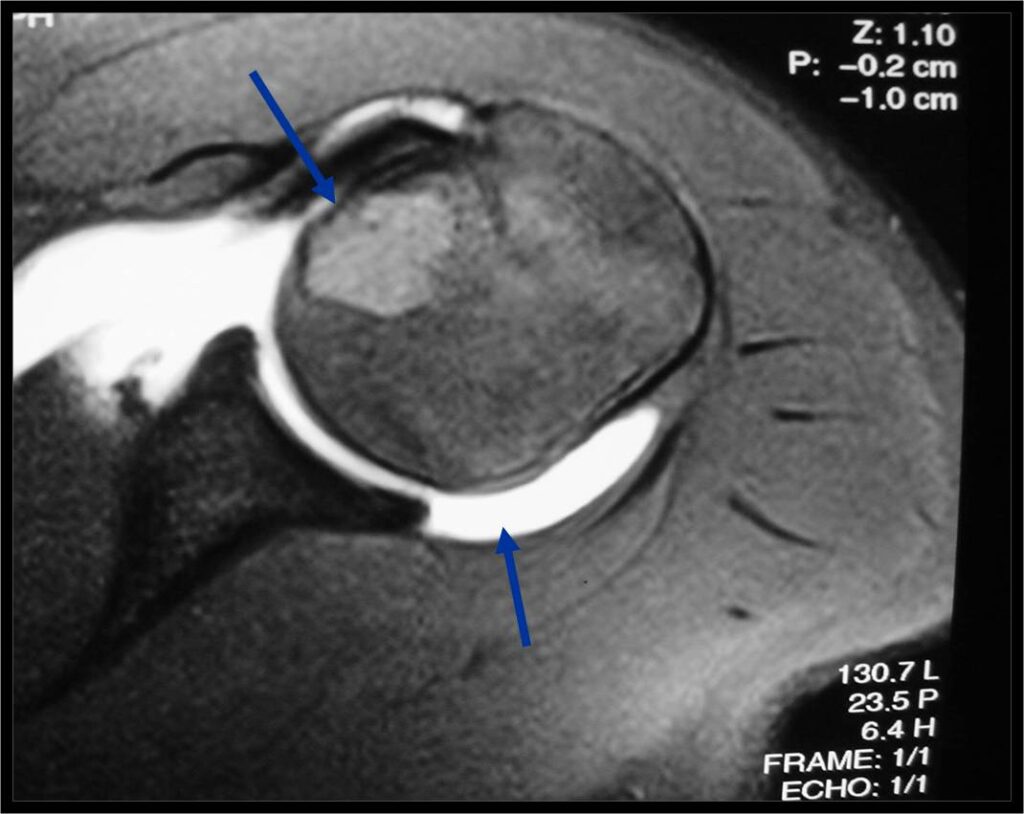

MRI appearance:

- Geographic, well circumscribed lesion in the epiphysis

- Intermediate Signal on T1

- High signal on T2 mixed with low signal areas (low signal areas proposed to be secondary to lysosomal content of highly cellular areas)

- Fluid/Fluid levels demonstrated in tumors that have undergone ABC change (aneurysmal bone cyst change)

- Extensive Surrounding edema is common

- Joint effusion in 30-50% of cases

- Predilection for distal femur, proximal tibia & humerus

- Proximal Humerus 17%